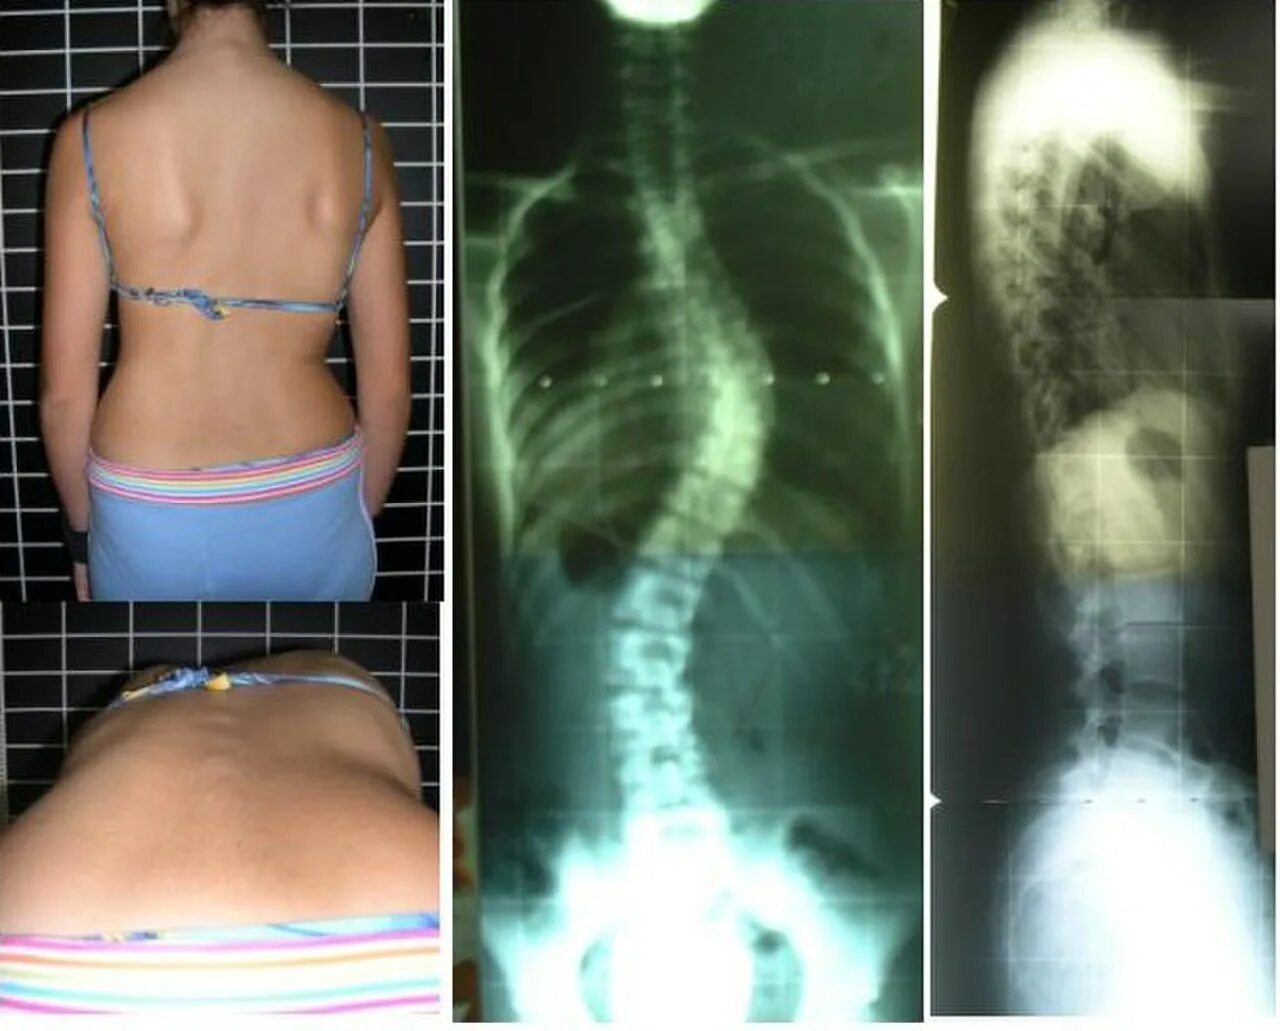

Гипоплазия 12 пары ребер